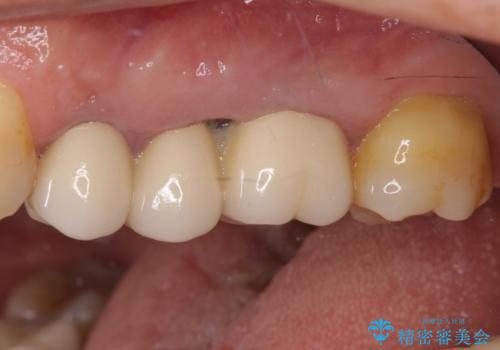

ものが挟まって痛む 割れてしまった歯のオールセラミックブリッジ治療

- 奥歯に物が挟まり、痛みを感じるとのことで来院された患者様です。

レントゲン写真より、歯が破折している可能性が示唆され、歯槽骨が大きく欠損している様子が分かりました。

3歯のクラウンを除去し、破折が疑われる歯をチェックしたところ、予想通り破折していたため、抜去することとしました。

抜歯後、骨吸収量が多く、歯肉のラインが不揃いとなっているため骨造成術を、硬い歯肉が失われて清掃性が低下するため角化歯肉の移植術を行い、また並行して支台歯の根管治療を行っていき、環境を整えた上でオールセラミックブリッジにて補綴治療を行うこととしました。